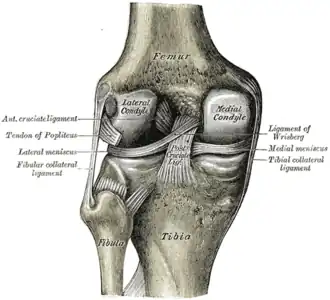

En el caso de la rodilla, hay un menisco en la parte interna de la rodilla (el menisco medial) y otro en la parte externa de la rodilla (el menisco lateral). Cada menisco está fijado a la parte superior del hueso de la pantorrilla (tibia) y también hace contacto con el hueso del muslo (fémur), actuando como amortiguador cuando la rodilla está soportando una carga.

Se encuentran adheridos a la periferia del platillo tibial mediante el ligamento meniscal. Aumentan la superficie articular de los platillos tibiales y la congruencia entre los cóndilos femorales y la tibia. Permiten una mejor distribución de la carga. Tienden a desplazarse hacia atrás en la flexión y hacia delante en la extensión. El menisco medial tiene menos movilidad que el menisco lateral.

Cada uno posee una forma característica: el menisco medial es una media luna más gruesa en su parte posterior y el menisco lateral es una porción grande en un círculo pequeño; su grosor puede ser homogéneo. Ambos meniscos son más gruesos en la periferia y más delgados en su borde interno. Estos meniscos ayudan a la lubricación y a la nutrición a través del líquido sinovial que liberan las sinoviales al realizar movimientos de flexo-extensión y cargas y descargas de peso.